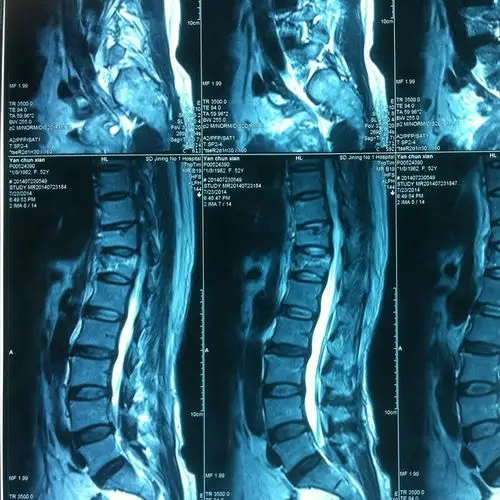

腰椎骨折保守治疗效果较好 病例分享